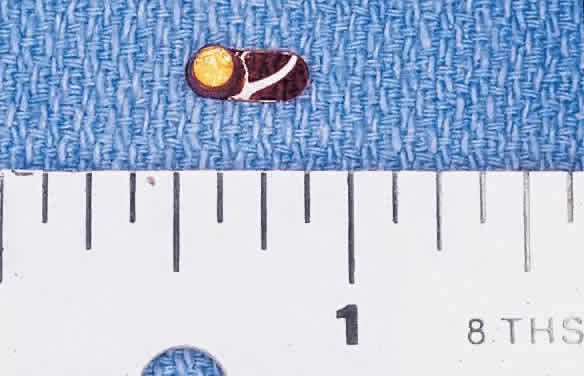

Rhegmatogenous retinal detachment occurs in 10% to 20% of eyes with CMV retinitis.37–39 However, before the AIDS epidemic, there were only five reported cases of this association.10,40 In patients living more than 1 year with CMV retinitis, risk of retinal detachment may be as high as 50%,41 which increases if more than 25% of peripheral retina is involved by disease.41,42 Retinal breaks in eyes with CMV retinitis typically occur within or at the border of necrotic atrophic retina (Fig. 6).43 The ensuing retinal detachments are typically difficult to repair with standard scleral buckling procedures. This is because of the location and number of retinal breaks, the difficulty in visualizing all breaks in necrotic retina, and the high incidence of associated proliferative vitreoretinopathy. In many cases, pars plana vitrectomy and retinal tamponade with silicone oil or long-acting intraocular gas is indicated (Figs. 7 and 8).37,44,45 However, scleral buckling may be considered in small peripheral retinal detachments when the entire involved area can be completely placed on the element. Laser photocoagulation demarcation has also been described to delimit macula-sparing CMV-related retinal detachment.46 Although anatomic success of macular reattachment with surgery is high, the visual results are often limited by the underlying disease process.47 When considering surgical repair of CMV-induced retinal detachment, consideration should be given to the potential for ambulatory vision, the patient's systemic condition and the status of the fellow eye.